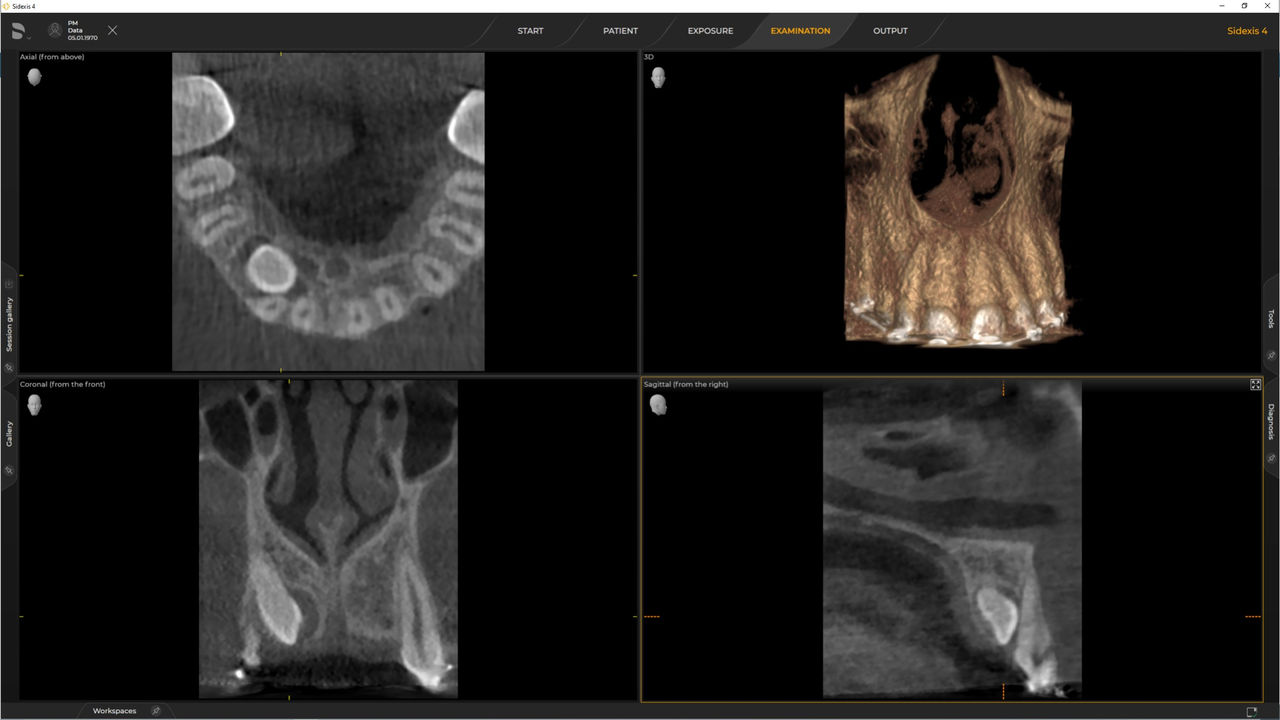

De Ø 5 cm x 5,5 cm a 8 cm x 8 cm u opcional hasta 11 cm x 10 cm

Con el modo de dosis baja inteligente 3D, obtiene imágenes 3D en el rango de dosis de una imagen radiológica 2D. En el modo HD (hasta 1400), las imágenes individuales se obtienen durante una única rotación y se convierten en un volumen 3D con hasta 80 μm para imágenes de bajo ruido en alta resolución.

Una amplia gama de tamaños de volumen para satisfacer sus diversas necesidades clínicas y de diagnóstico, desde Ø 5 x 5,5 cm hasta Ø 11 x 10 cm

Las unidades de radiología de Dentsply Sirona funcionan exclusivamente con Sidexis 4. Sin embargo, la migración de datos de Sidexis XG a Sidexis 4 es muy fácil. Sidexis 4 permite una experiencia digital completa con las últimas herramientas